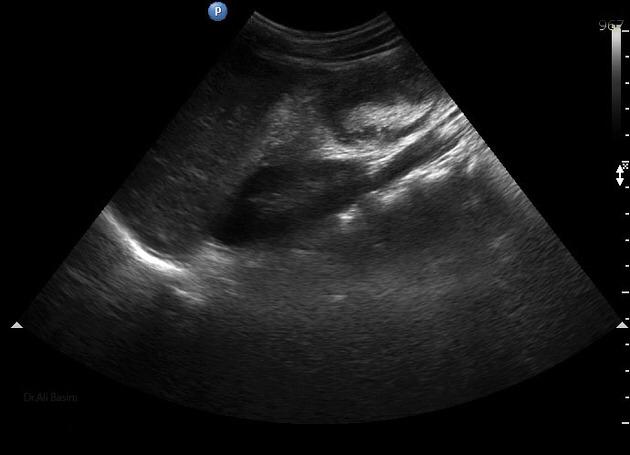

La invaginación intestinal es la causa más común de obstrucción intestinal en niños de 3 meses a 3 años. Se caracteriza porque un segmento de intestino penetra en otro segmento intestinal. Puede presentarse en colon, intestino delgado o entre intestino delgado y el colon. El resultado es la obstrucción intestinal.